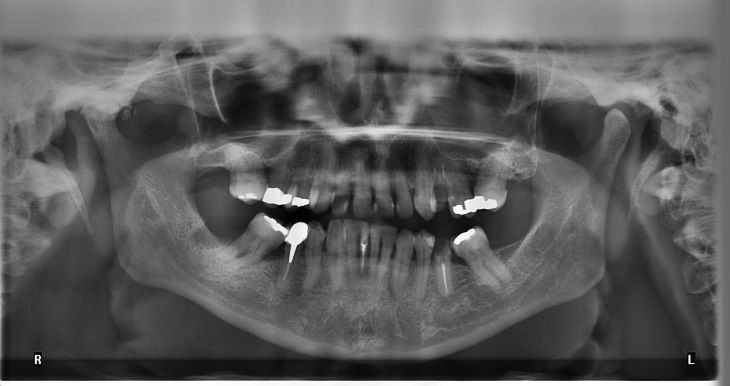

Композитный материал, который создали разработчики Орегонского университета здоровья и науки, должен в разы увеличить срок службы пломб.

Эксперты уверяют, что, в сравнении с обычными пломбировочными материалами, его устойчивость к разрушениям практически в два раза выше.

Научные сотрудники подчеркивают, что применение их новинки в два раза продлит срок службы зубных пломб.